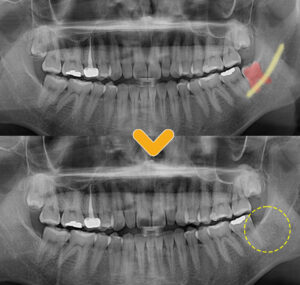

전반적인 엑스레이 촬영 결과,

환자분께서는 위쪽 양옆에 2개,

아래 왼쪽에 1개의 사랑니가 존재하였고,

환자분께서 불편해 하시는

왼쪽 아래의 사랑니는

잇몸뼈에 완전히 매복되어 있는 상태였습니다.

환자분의 왼쪽 아래의 사랑니는

다행히 누워있는 형태는 아니었으나,

치아 뿌리의 형태가 많이 휘어 있어

발치를 진행하는 과정에서

부러질 수 있는 가능성이 있었으며,

아래턱뼈를 가로지르는 하치조 신경관과

거리가 매우 가까운 케이스로

난이도가 높은 편에 속하였습니다.

충분한 상담 후 사랑니 발치를 진행하였고,

깔끔하게 발치가 완료된 모습입니다.

사랑니 치아의 뿌리가 많이 휘어있었고,

신경과 매우 가까운 상태였으나

신경의 손상이 없이,

뿌리와 잔여물 없이 깔끔하게 제거가 되었습니다.